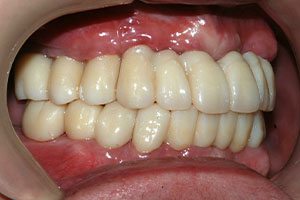

치료증례 전후사진

Before & After